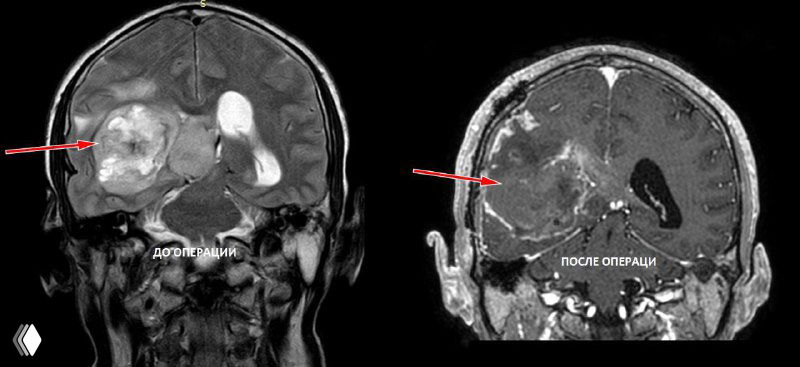

На снимках - глиобластома заполняющая больше половины правого полушария головного мозга.